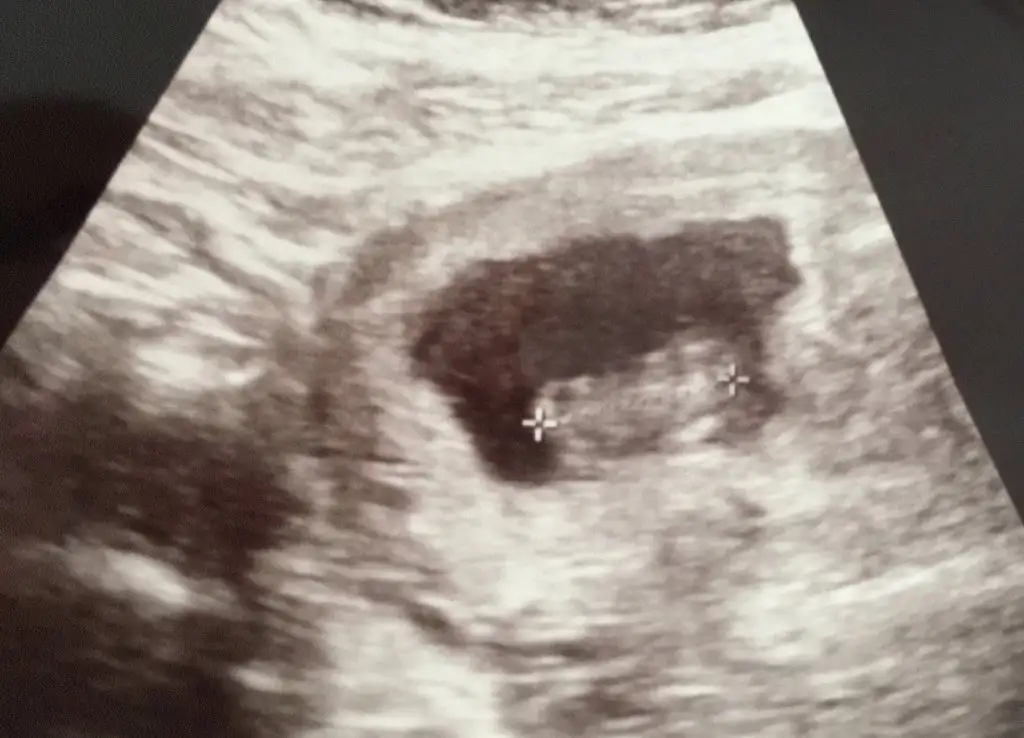

İlk fotoğraf 12+0

İkinci fotoğraf 12+3 (doktor çıkıntı gördüm sanki ama kesin değil dedi)

Üçüncü fotoğraf 14+2 (kız gibi dedi ama bakmaya devam ederken aaa pipi bu ama yine de emin olmak için 1-2 hafta sonra tekrar bakalım dedi)

son fotoğraf da gördüm dediği pipi